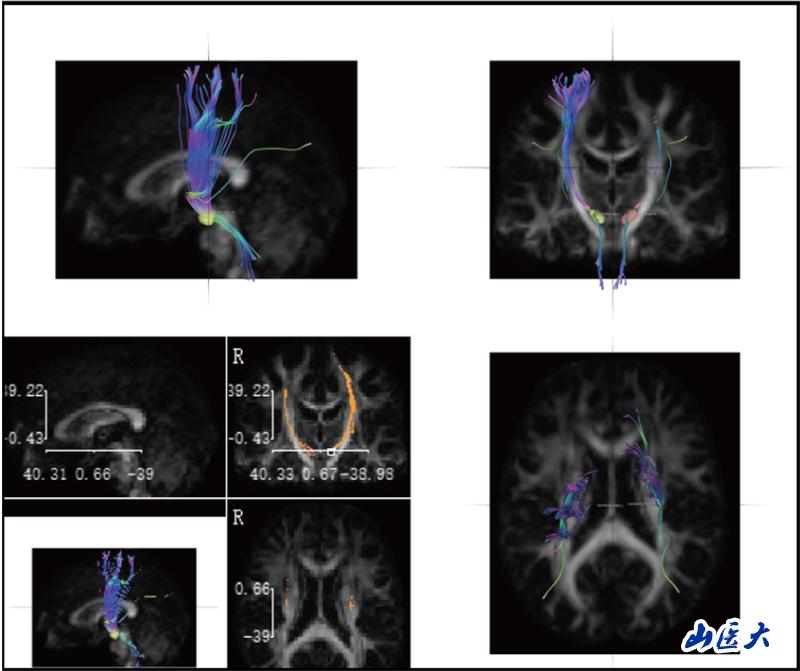

神經解剖學教學長期面臨"結構隱匿性"與"空間復雜性"的雙重挑戰。傳統的大體標本和平面模型難以展現纖維束、核團等微觀結構的空間關系,易導致學生神經解剖結構認知困難。研究團隊針對這一痛點,創造性引入前沿神經影像技術—DSI Studio纖維束成像系統。該技術通過對擴散磁共振成像(dMRI)數據分析,實現纖維路徑智能追蹤、三維動態重建及多維度交互可視化,構建起"影像解剖-病理對照-臨床關聯"的一體化數字教學體系。

研究團隊創新性構建"理論-操作-臨床"三階整合教學模式,基于DSI Studio纖維束成像技術開展教學實踐。選取38名低年級醫學生為對象,通過整合人類連接組計劃(HCP)標準腦數據庫、帕金森病進展標志物計劃(PPMI)及臨床腦出血病例影像數據,建立"正常-病理"雙模態教學資源庫。此教學實踐改革,不僅提升了學生神經解剖結構的空間理解力,并培養了學生從解剖結構認知到功能損傷解析的臨床思維能力。